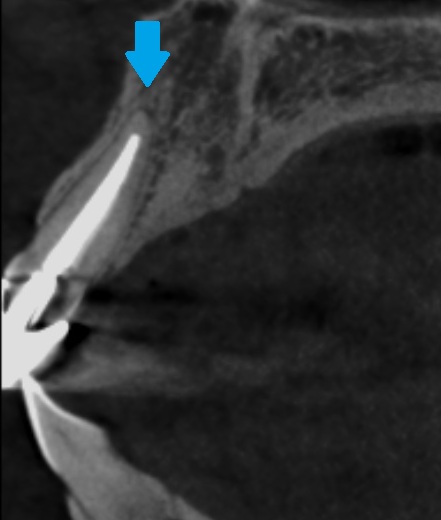

CT写真でさらに詳しく確認してみると、

正面と横側からの断面です。

神経を抜いてある歯を治療する際には、根の先で膿んでいないか(バイ菌が入っていないか)を確認する必要があります。

神経が無いので、虫歯が入り感染していても痛みを感じません。

もしバイ菌が入っている場合は、再度、根管治療を行ない、歯の中を消毒する必要があります。

今回は問題ないので、差し歯(かぶせ物と土台)だけやり直します。